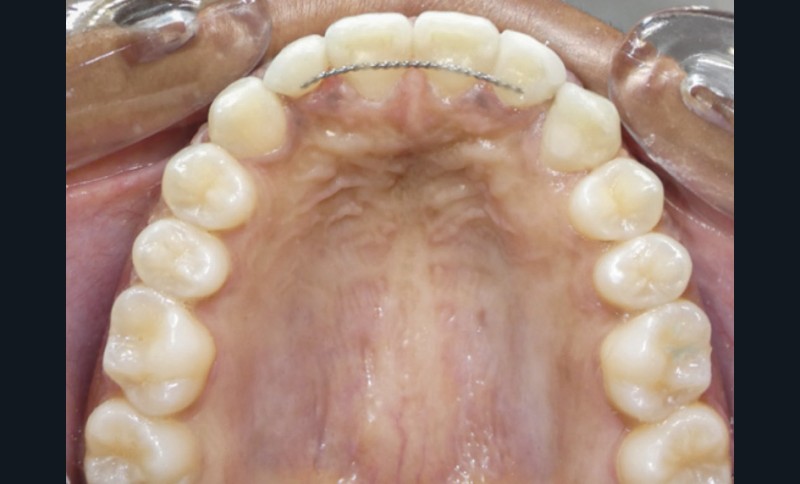

Contention

La contention sera assurée par fil collé maxillaire (après réalisation des restaurations composites) et mandibulaire, ainsi qu’une gouttière thermoformée à port nocturne à l’arcade maxillaire.